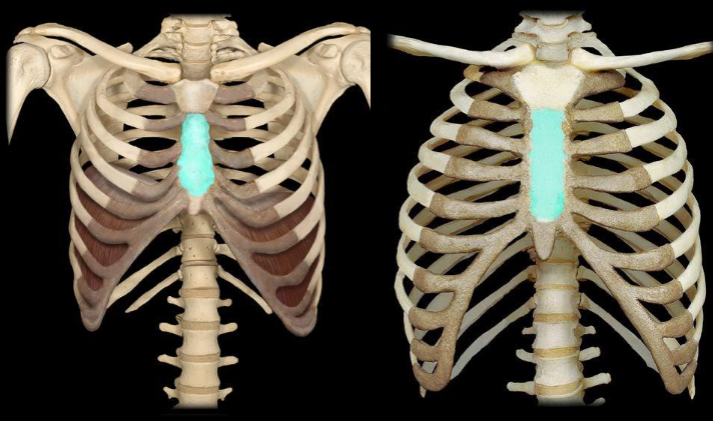

What bone is highlighted in this image?

sternum

What part of the sternum is highlighted in this image?

body of the sternum (longer part)

What part of the sternum is highlighted in this image?

manubrium (smaller & pentagon shaped)

What part of the sternum is highlighted in this image?

xiphoid process (tip)